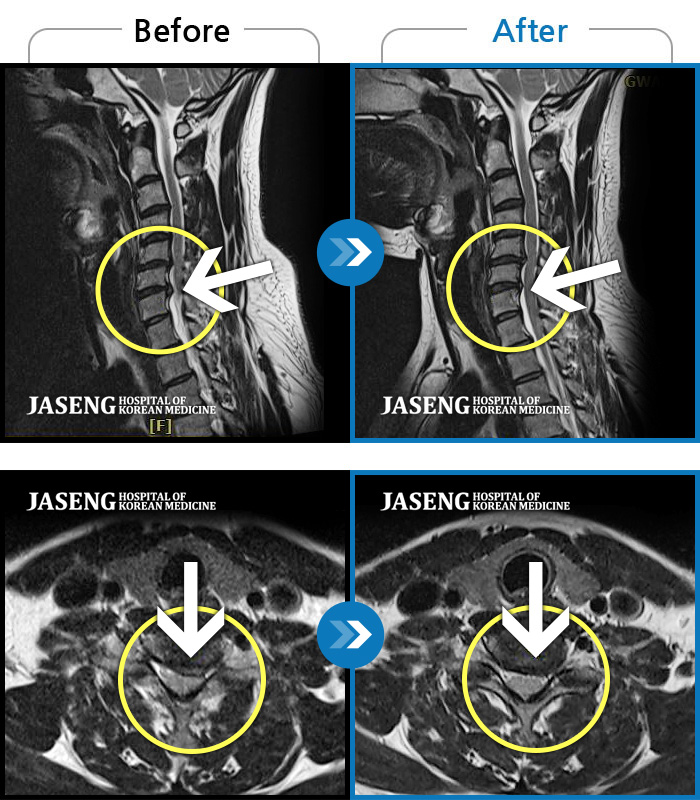

자생 비수술 한방통합치료 후

터진디스크가 흡수된 모습

Before

After

비수술 치료만으로

터진 디스크 흡수